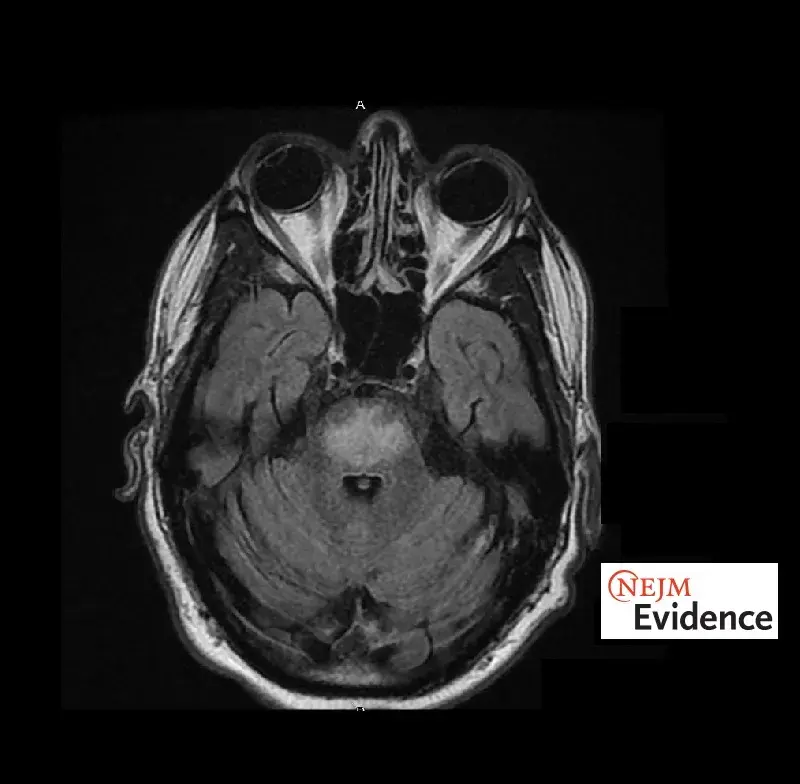

Síndrome de Desmielinización Osmótica: ¡Rara, pero potencialmente grave!

Síndrome de Desmielinización Osmótica: ¡Rara, pero potencialmente grave!